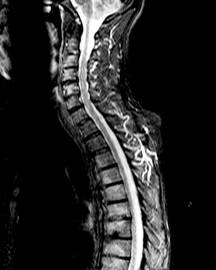

Figure 1. Example images of a patient with minimal-change chronic pancreatitis. This 40-year-old woman presented with upper abdominal pain that worsened with fatty foods. Computed tomography (top) showed a relatively normal pancreas. (Arrows delineate the borders of the body of the pancreas.) Endoscopic ultrasonography (bottom) showed several criteria for chronic pancreatitis, including an ectatic main pancreatic duct (black arrows), visible side branches (red arrow), and nonshadowing echogenic foci (white arrow head).

It is impossible to know the “true” accuracy of EUS because of the heterogeneity of design and inherent limitations of these studies. However, we can reasonably deduce that EUS is sensitive for mild chronic pancreatitis, even early in its course before computed tomography can reveal calcifications or atrophy (Figure 1).